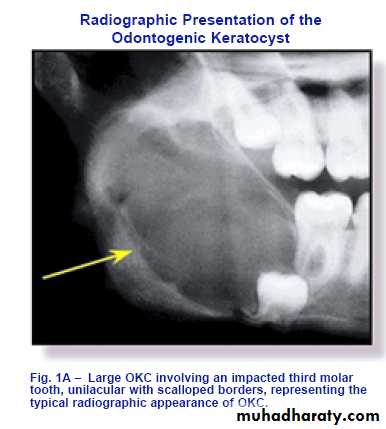

OKC may be confused radiographically with ameloblastoma or with Dentigerous cyst.Spread extensively through marrow space before expanding the jaw

May be part of the jaw cyst/ basal cell naevus syndrome.radiographical features

Appear as well defined radiolucent area more or less rounded with a scalloped margin, or multiloculated radiolucency resembling ameloblastoma.The bony wall appear sharply demarcated.

It may envelop an unerupted tooth and in this case it may be indistinguishable from dentigerous cyst.

Roots of the adjacent teeth may become displaced.